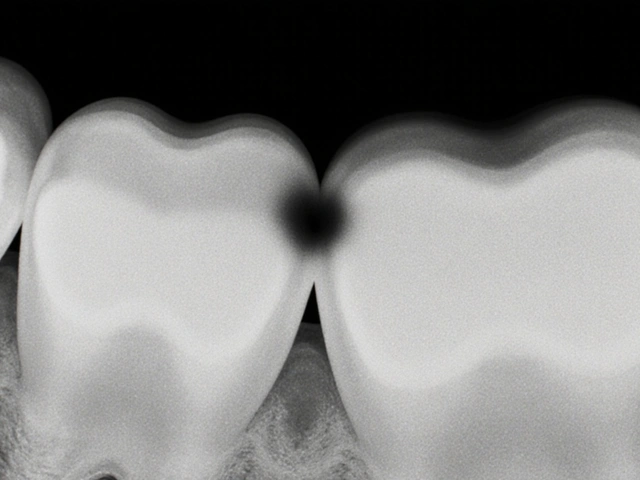

Jak vypadá začátek zubního kazu na rentgenu?

Začátek kazu na rentgenu vypadá jako malá tmavá skvrna na povrchu zubu, obvykle na mezizubních plochách nebo v hlubokých drážkách. Je to mírná ztráta hustoty skloviny, která je ještě malá a nepronikla do dentinu. Na začátku je možné ji zastavit fluoridovou léčbou a lepší hygienou.

Ano, pokud je rentgen špatně natočený nebo pokud lékař nezkontroluje všechny části snímku. To je důvod, proč je důležité, aby se rentgen dělal pravidelně a posuzoval odborník. Některé malé kazy mezi zuby jsou velmi těžké zjistit i na dobrém snímku.